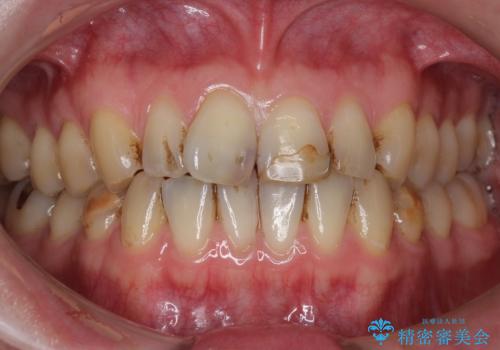

- 前歯のプラスチックの詰め物が気になると来院された患者様です。

左上の前歯に詰められたプラスチック(コンポジットレジン)は、劣化し変色していました。

レジンを除去したところ二次う蝕を認めたため、丁寧に虫歯をとりました。

歯の欠損範囲が大きいことから、同様にレジン修復しても欠けやすいためセラミッククラウンによる補綴を行いました。

患者様のご希望により、最終補綴前にホワイトニングを行いました。